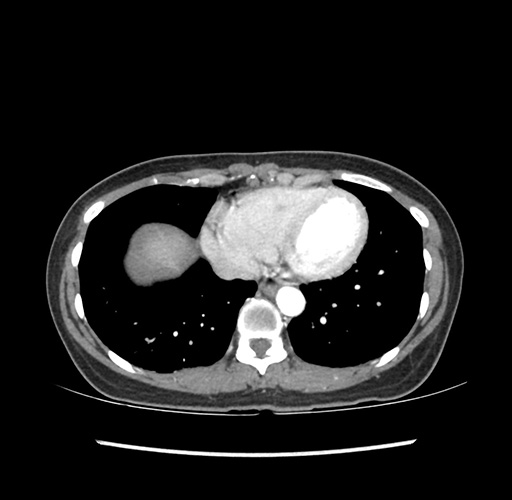

Imaging Analysis

Look through the patient's CT scan to identify any areas of concern for the necessary procedure.

Based on your CT findings, which issue(s) would give reason for "planned slowing down moment(s)" in this case?